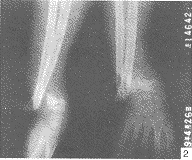

肘关节脱位并尺桡骨远端骨折1例

肘关节脱位|尺骨骨折|桡骨骨折|儿童,关键词:

肘关节脱位;尺骨骨折;桡骨骨折;儿童